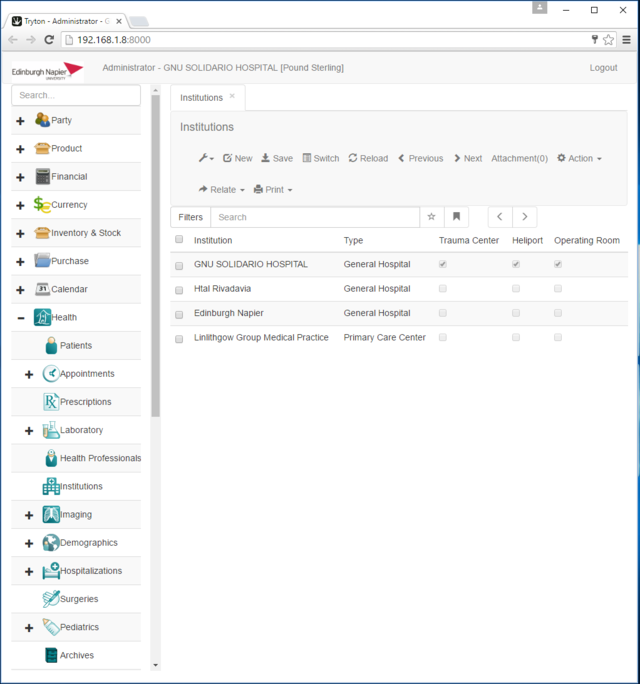

1. GNU Health Web Interface

- 4 x GNU Health application running on the Tryton Server, installed on Ubuntu 16

- 4 x GNU Health application running on the Tryton Server, installed on Raspbian

- 1 x GNU Health application running on the Tryton Server and a database on a PostgreSQL Server, installed on Raspbian